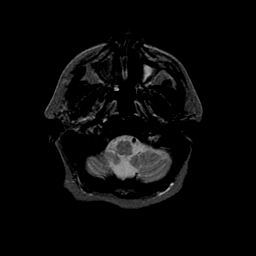

Basal Ganglia Calcification: T2-weighted MR -- Slice #2

[Home][Help][Clinical] Slice 2